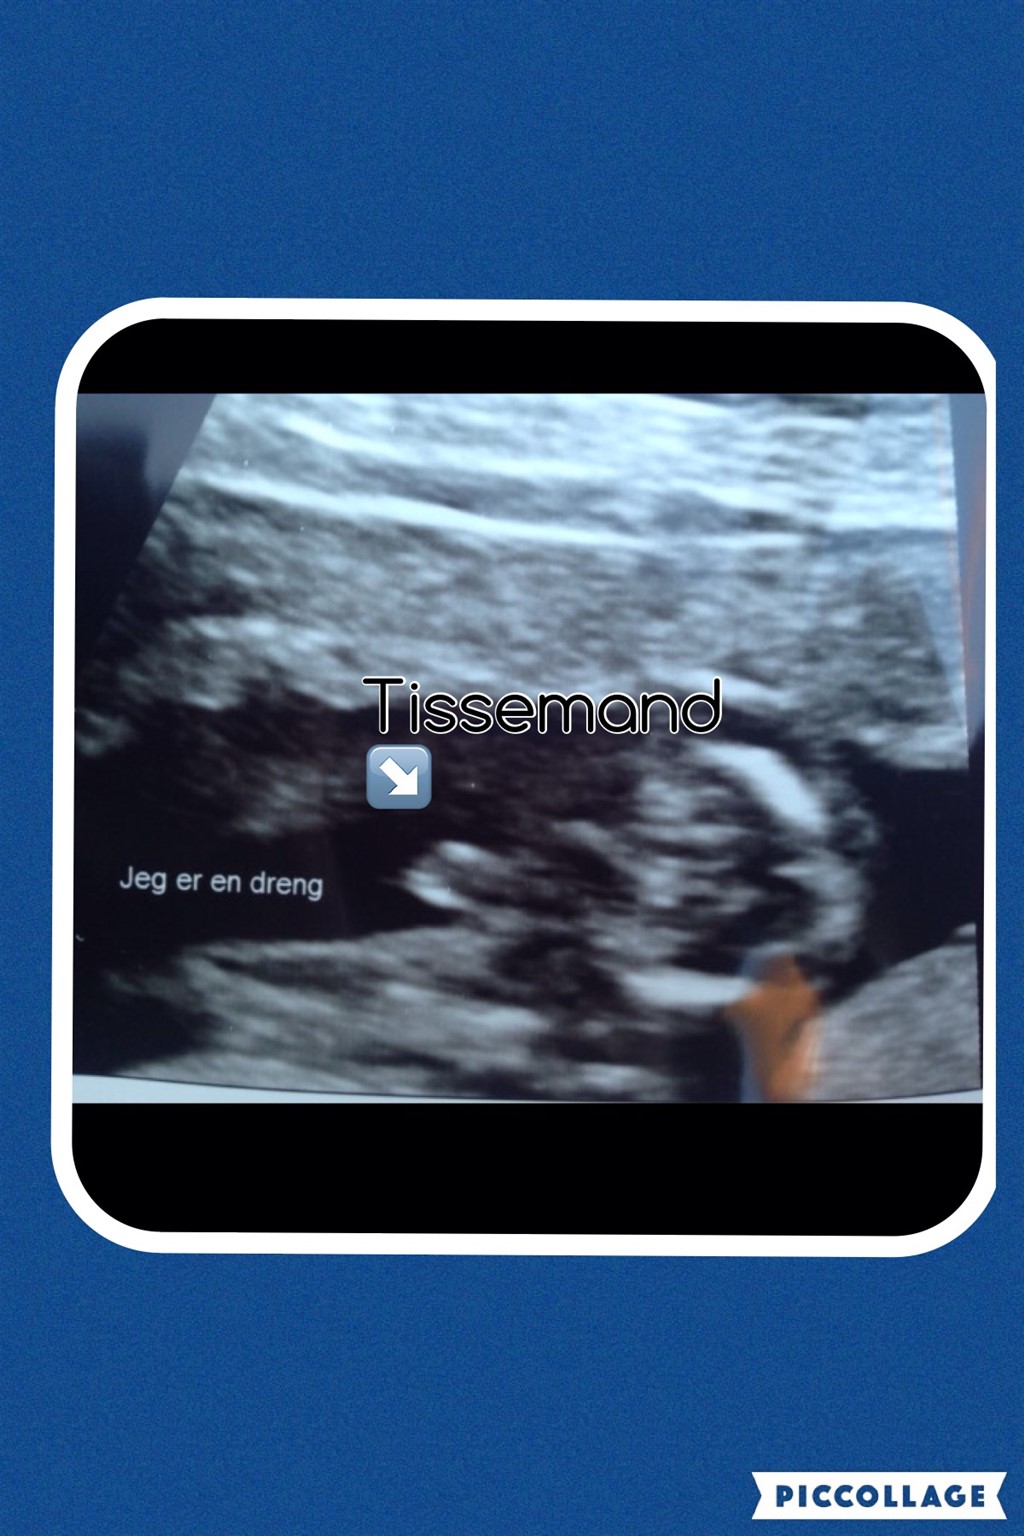

Vores lille bandit ville ingenting da vi var til kønsscanning(14+3), men så lige pludselig var der bare kønsdel på hele skærmen

Vi er i hvert fald ikke i tvivl (selvom hun snød og skrev det på skærmen)